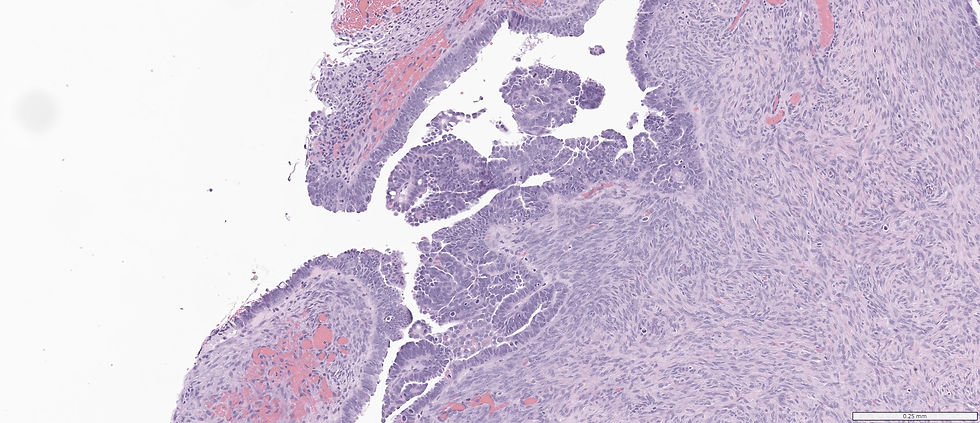

A 56-year-old female with some focal lesion on the ovary.

This is a case of high grade serous carcinoma. Although low power field, serous borderline tumor might be in the ddx, high power field of significant cytologic atypia and mitosis are obvious.